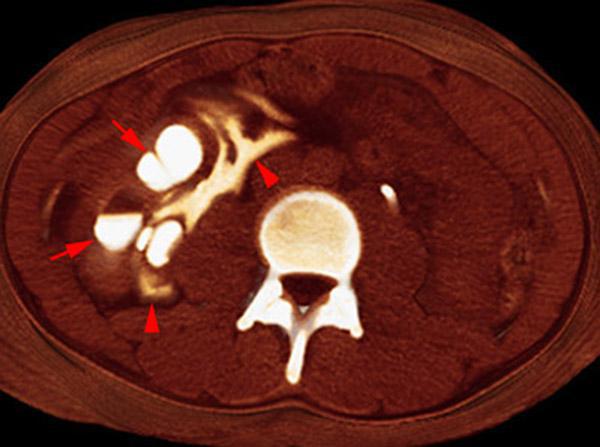

Hematoma subcapsular